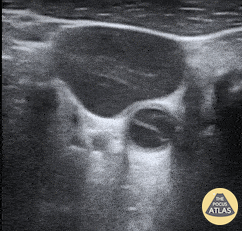

A middle aged patient presented with severe chest pain without associated neurologic deficits. CTA revealed a Type A aortic dissection with equivocal carotid extension. Subsequent POCUS seen here confirmed presence of a mobile echogenic intimal flap consistent with carotid artery dissection. Michael Cover, MD @michaelc0ver